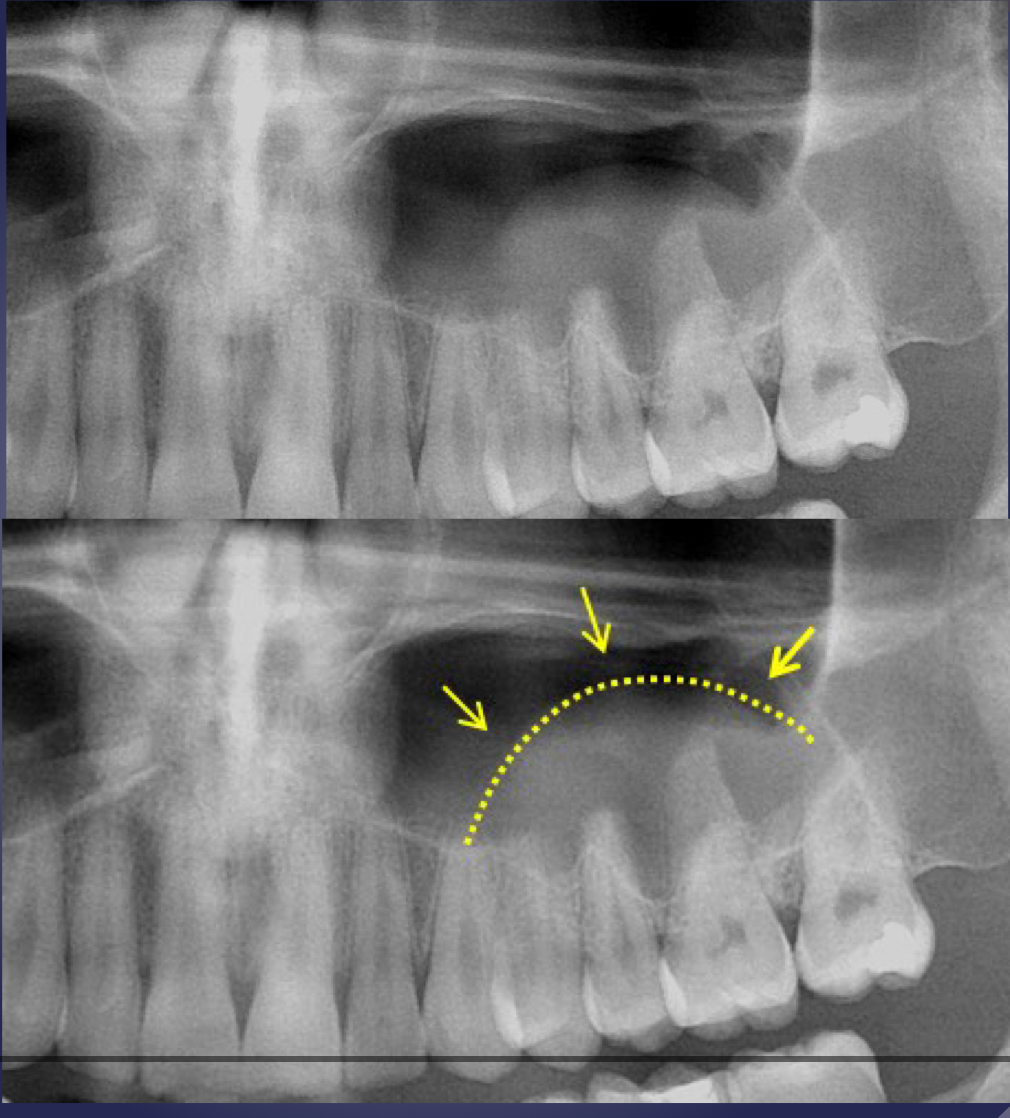

what’s going on here?

what is going on here?

pathological fracture, facture on a compromised boone